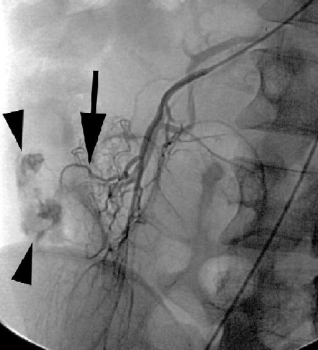

Hình 9: DSA thấy máu đang chảy từ túi thừa Meckel ở bệnh nhân nam 26 tuổi với triệu chứng đi cầu ra máu. Bơm thuốc ở

động mạch hồi đại tràng thấy xuất huyết ở nhánh gần (mũi tên). Thuốc cản quang thoát vào lòng ruột non (đầu mũi tên).

(Angela D. Levy, Christine M. Hobbs (2004). Meckel Diverticulum: Radiologic Features with Pathologic Correlation. RadioGraphics; 24:577)